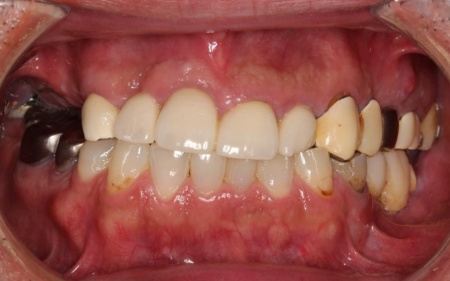

40代女性 乱れた歯並びと不安定な噛み合わせを矯正治療と被せ物で改善した症例

- 矯正歯科

- ワイヤー矯正

- 詰め物・被せもの

- セラミック・ジルコニア

- 抜歯

- ダイレクトボンディング

- 治療期間の目安 4年

- 治療回数の目安 45~50回

-

治療費総額の目安

約2,370,000円

(矯正治療、ジルコニアクラウン、ダイレクトクラウン)

治療のリスク

・外科処置後に痛みが長引く場合があります。必要に応じ痛み止めを併用します ・治療中、装置によってまれに頬の内側が傷つき、口内炎になる場合があります ・歯の移動に伴って、違和感や痛みを感じる場合があります ・正しいブラッシングやメンテナンスを行わない場合、虫歯や歯周病のリスクが高まります ・装...

by.鈴木歯科医院